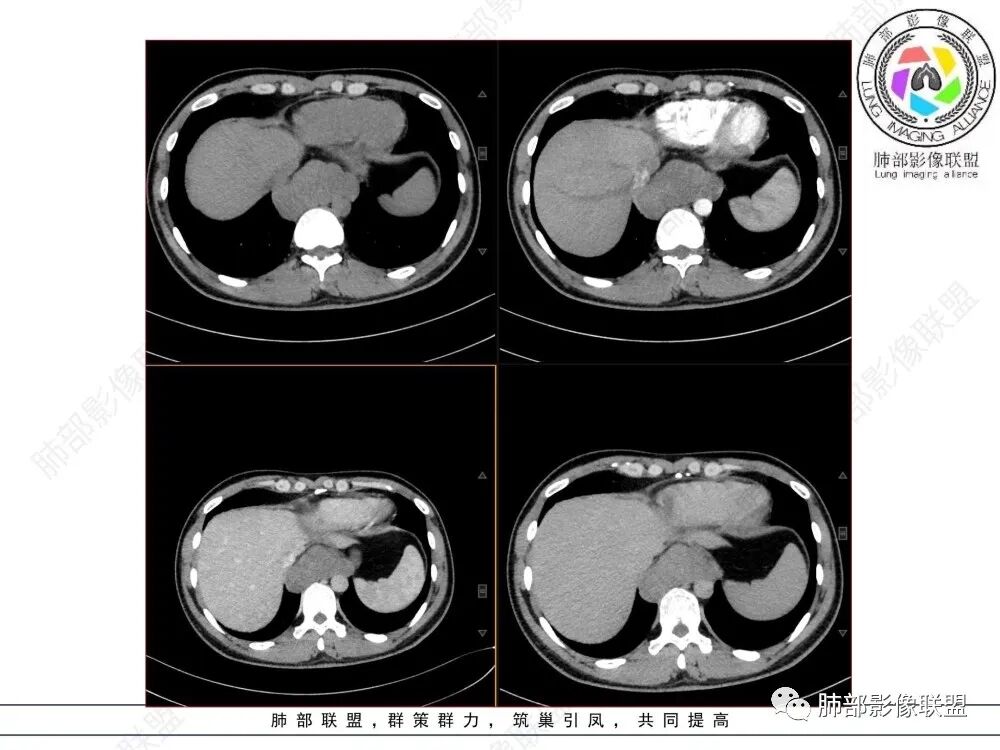

年轻男性,食管下段占位性病变长轴平行于食管,平扫密度尚均匀,增强轻度强化,MRI示T1、T2低信号,DWI低信号。考虑来源于食管,考虑平滑肌瘤或神经鞘瘤>间质瘤

定位后纵膈,这个位置,神经,淋巴,食管,轻微强化,T2低信号,弥散受限,考虑平滑肌瘤,鉴别神经原性。

平滑肌瘤(食管下段团块状肿块,环食管生长,分叶密度均匀,增强轻度强化。钡餐时食管受压移位,T1 T2 DWi低信号,病变来源于食管,考虑平滑肌瘤)

定位后纵膈,实性密度,增强轻度强化,T1等低信号T2低信号,弥散未受限。钡餐造影,食道及贲门管壁柔和,造影剂通过顺畅。考虑神经鞘瘤。鉴别食道平滑肌瘤。

轻度强化,等T1等T2,弥散不受限,密度及信号相对均匀,感觉后壁来源并食管受压推移,考虑平滑肌瘤。

T2低信号是关键,提示平滑肌细胞

食管平滑肌瘤是最常见的食管良性肿瘤,多见于男性,男女之比为2.6:1,高发年龄 30~60岁之间与食管癌相比,食管平滑肌瘤 的一个主要特点是病史相对较长,病情进展缓慢。病史最长者达10年余,平均 15.7个月,尽管病史较长,但大多数患者仍能进普食。食管平滑肌瘤的诊断一般比较容易,结合患者临床症状、食管造影及食管镜所见,一般均能得出正确诊断。食管造影主要为充盈缺损,病变与食管壁成锐角,粘膜线连续无破坏,管腔收缩扩张比较自如。钡餐造影敏感性高,但对食管壁间及食管周围情况难以判断。CT具有极高的密度分辨率,并且可以获得高质量的多平面重组图像,有利于食管壁间及食管周围情况的判断,表现为食管下段环绕管壁生长,偏心性或薄厚不均软组织密度肿块,密度均匀,内缘分叶状,管腔与正常食管壁构成不规则多角形扩张,增强动脉期无强化,多角度重建其病灶长轴与食管长轴不一致。由于食管壁在收缩状态下厚度约为5.6mm,扩张状态厚度不超过3mm,CT扫描时保持食管处于扩张状态可提高小病灶检出率。MR表现为T1加权等信号,T2加权稍高信号,可见高信号粘膜层,增强扫描轻度渐进性强化,密度均匀,无出血坏死。对于粘膜及周围脂肪间隙的判断具有明显优势。